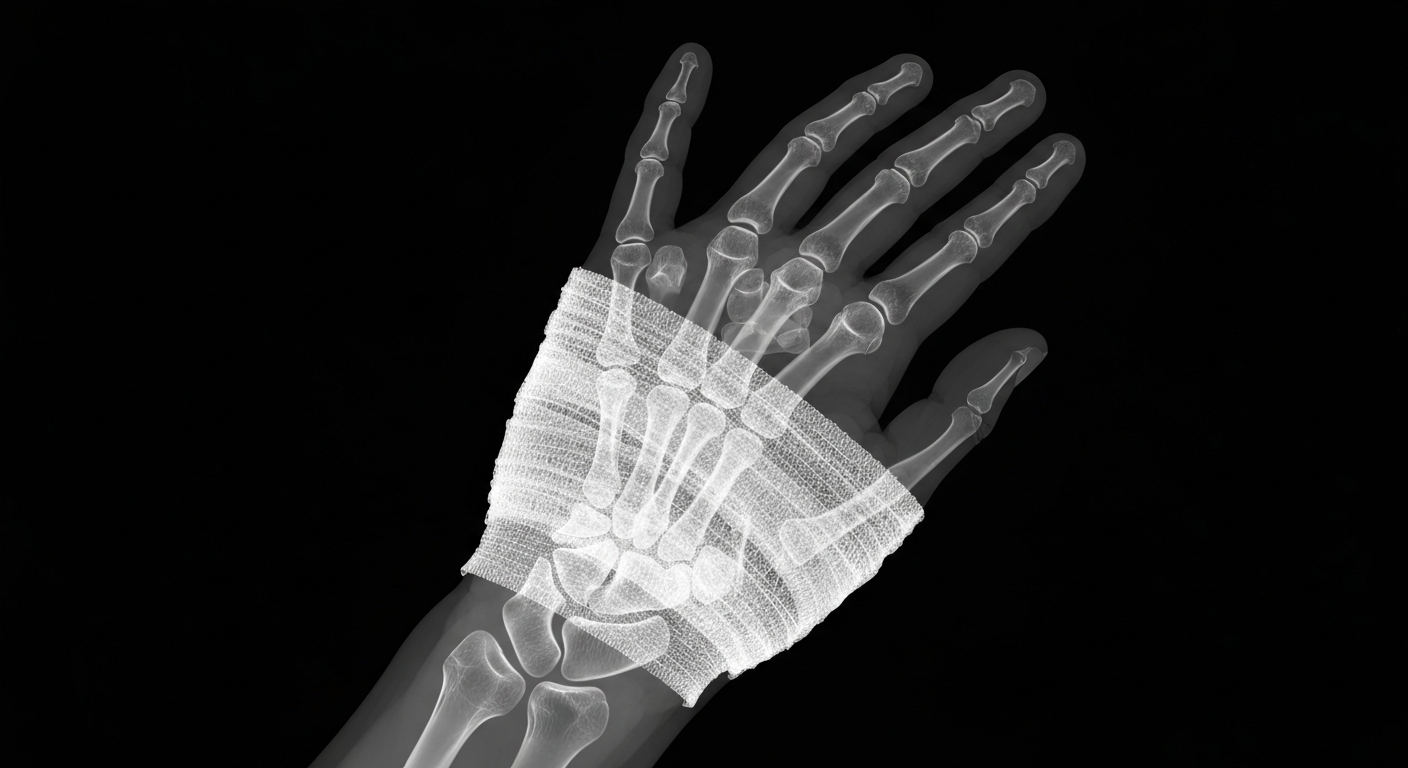

An X-ray view exposes the internal structure of a bandaged hand, underscoring the importance of sterile, contaminant-free wound care products.Santa Fe Springs TodayBlaine Labs, Inc., a pharmaceutical company based in Santa Fe Springs, California, has issued a voluntary nationwide recall of several of its wound care gel products due to potential microbial contamination. The recall affects multiple product lots that were distributed across the United States.